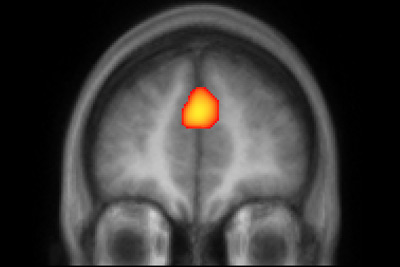

The researchers found that different patterns of brain activity in the medial prefrontal cortex (mPFC) were associated with each of the four different personalities. In other words, which person was being imagined could be accurately identified based solely on the brain activation pattern.

The results suggest that the brain codes the personality traits of others in distinct brain regions, and that this information is integrated in the mPFC to produce an overall personality model used to plan social interactions, the authors said.